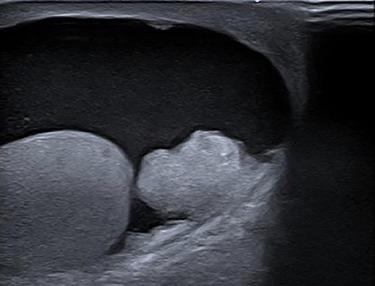

Metastases of colorectal carcinoma (CRC) in the testis are very rare and indicate an advanced stage of disease. In this case report, we present a patient with adenocarcinoma in the sigmoid colon with metastasis in the right testis. Testicular metastasis of CRC is mostly diagnosed late because of their low incidence rate. Patients with CRC and testicular metastasis have a poor prognosis. In this case, the patient turned out to have peritoneal metastasis and one should be aware that testicular metastasis could be the first sign of widespread disease.

结直肠癌(CRC)转移至睾丸非常罕见,提示疾病已处于晚期。在本病例报告中,我们呈现了一名患有乙状结肠癌并伴有右侧睾丸转移的患者。由于结直肠癌睾丸转移的发生率较低,其大多在晚期才被诊断出来。患有结直肠癌并伴有睾丸转移的患者预后较差。在本病例中,该患者最终被发现有腹膜转移,应意识到睾丸转移可能是广泛疾病的首个迹象。